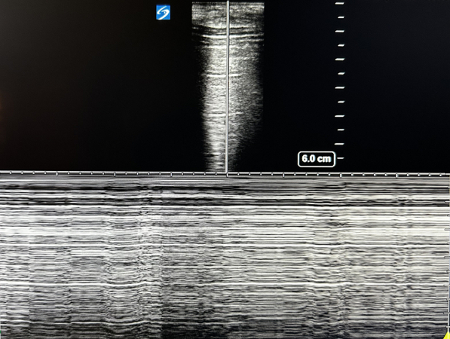

POCUS of the lung in a large pneumothorax. Shown is the ultrasound view showing A-lines that are reverberations of the pleural line. There is a lack of B-lines, which is also consistent with a pneumothorax. M-mode is placed on the patient and shows a ‘barcode sign’ confirming presence of air in the pleural space

From the personal collection of Chris Kapp, MD; used with permission